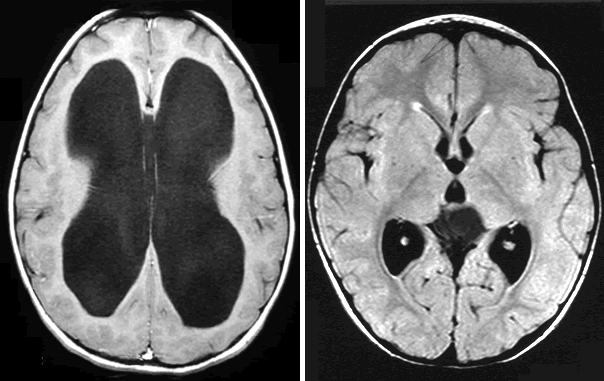

Researchers say the complementary use of artificial intelligence may significantly improve the accuracy of radiologists in diagnosing intracranial aneurysms.